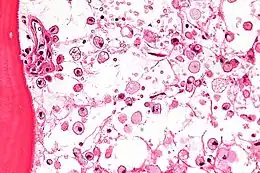

Une maladie lysosomale est une maladie, généralement génétique, de l'enfant et de l'adulte, en rapport avec le fonctionnement anormal d'une des enzymes contenues dans le lysosome.

On dénombre une cinquantaine de maladies lysosomales, dont le point commun est une déficience génétique aboutissant au dysfonctionnement du lysosome. Les lysosomes sont des organites du cytoplasme qui contiennent des enzymes (spécifiquement, des hydrolases acides) qui sont chargées d'assimiler les déchets (appelés métabolites) produits par les cellules. Cette assimilation est le travail de protéines produites par le lysosome. Pour chacune des maladies lysosomales, un défaut d'un gène spécifique entraîne la non-production ou la production insuffisante de la protéine chargée de l'assimilation des métabolites.

Les métabolites s'accumulent alors, entraînant le dysfonctionnement des organes concernés. La plupart de ces maladies sont évolutives et polyhandicapantes. Elles entraînent des handicaps physiques, et neurologiques pour certaines d'entre elles. Il s'agit dans tous les cas de maladies rares.